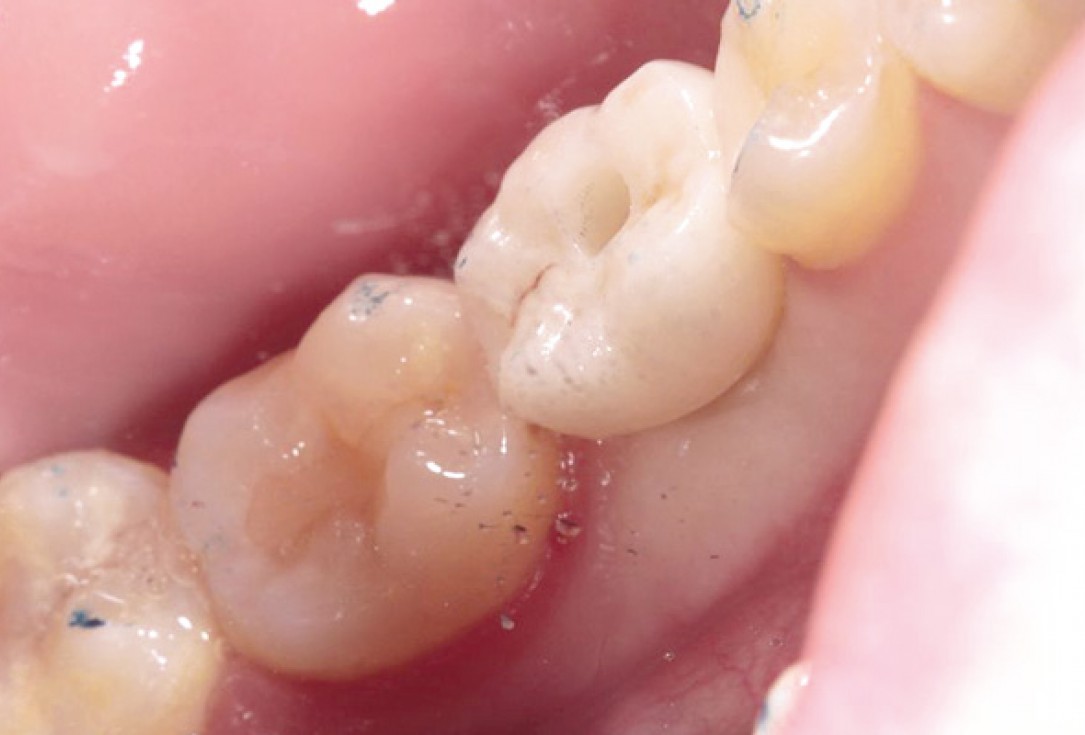

Situation after tooth extraction.